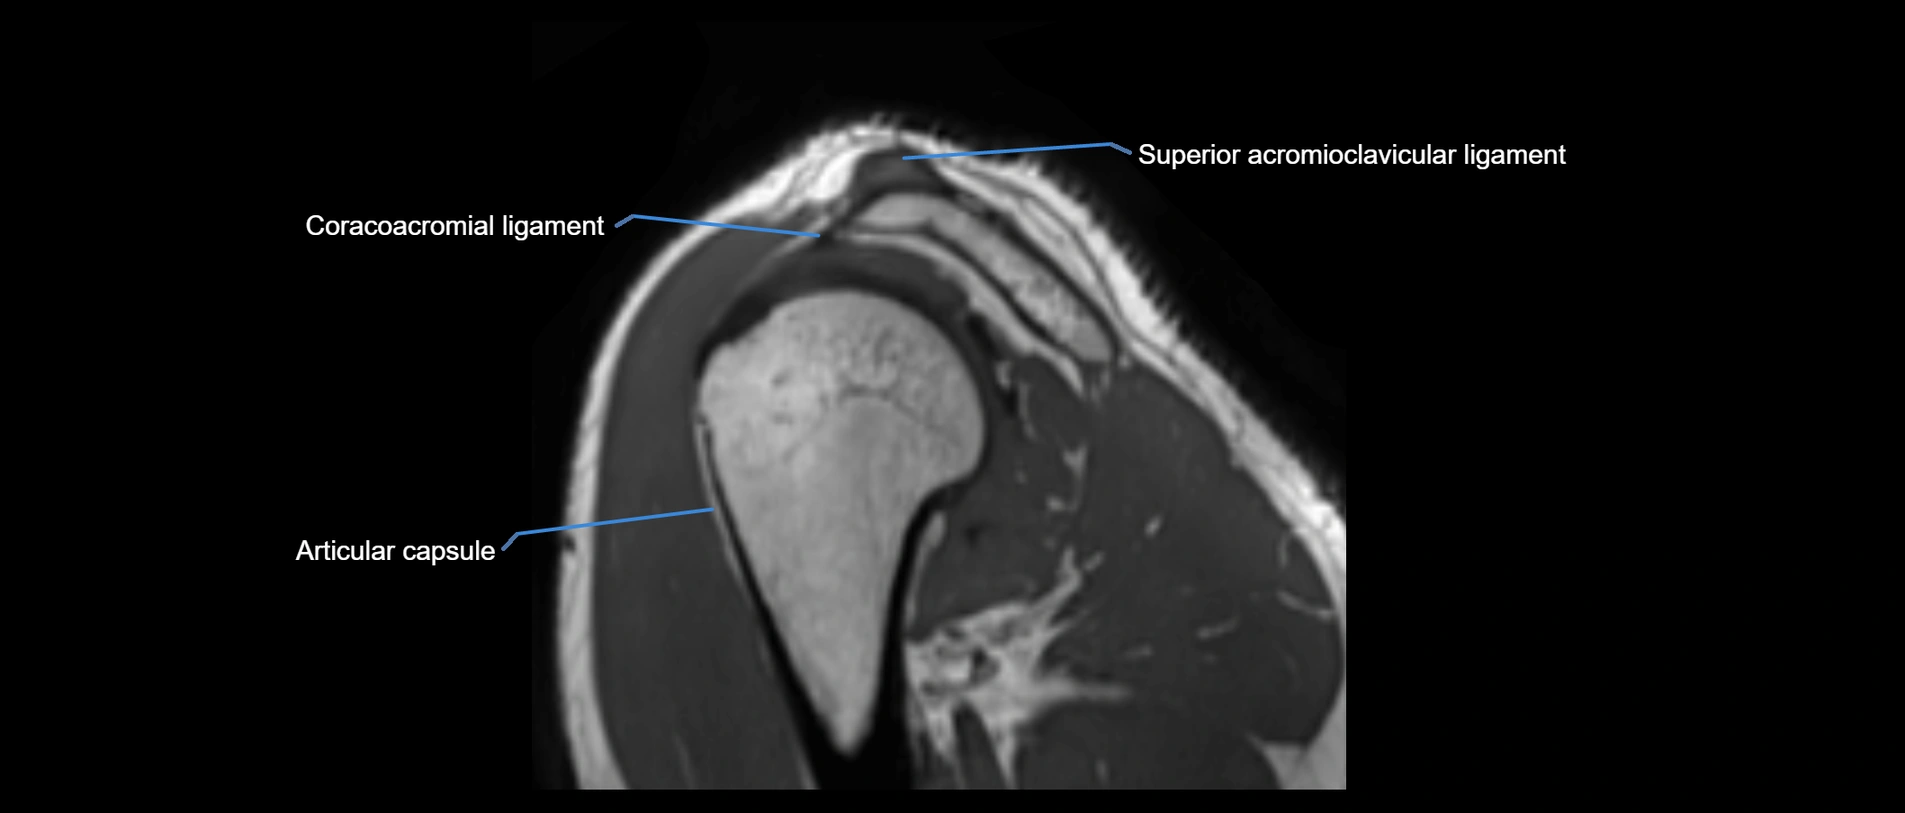

MRI Appearance

• T1-weighted images:

• Normal ligament: Low signal (dark linear band) spanning acromion to clavicle.

• Surrounding fat planes: Bright, delineating the ligament clearly.

• Marrow of clavicle and acromion: Bright due to fatty content.

• Tears: Discontinuity or irregular thickening with intermediate-to-bright signal.

• Chronic injury: Thinning, fraying, or irregular low-signal fibers with adjacent scarring.

• T2-weighted images:

• Normal ligament: Low signal, homogeneous.

• Partial tear or sprain: Focal hyperintensity or thickening.

• Complete tear: Discontinuity with fluid-bright gap between clavicle and acromion.

• Associated edema: Bright signal in distal clavicle or acromion marrow.

MRI images

image